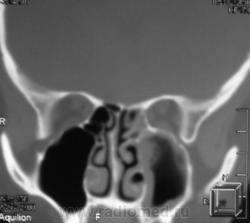

ППН.   Клиника гайморита.

Да, эксудативный левосторонний гайморит, в данной случае следует исключать одонтогенную природу, что более вероятно, вообще на данный момент на всех программных обеспечениях МСКТ, имеется мультипланарная программа с мощью которой все 2 ряда зубов как на ладони, с её помощью  удубнее оценивать состояние альвеолярных бухт, другое дело включена ли она в пакет приобреоенных программ.

Все-таки, гаймароэтмоидит: имеется содержимое в левых клетках решетчатого лабиринта. А почему одонтогенный? Зубы внедрены в пазухи с обеих сторон, оценить состояние периапикальных мягких тканей слева из-за жидкости не предсталяется возможным.